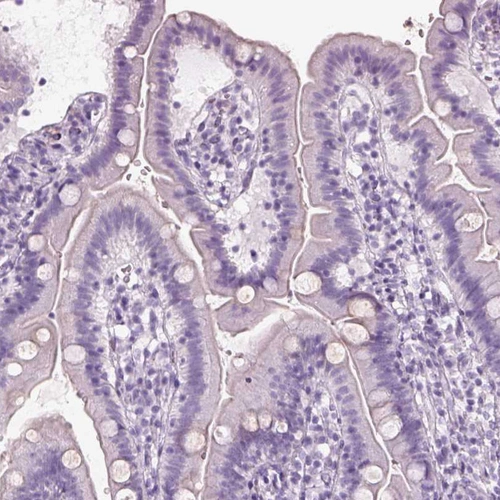

Immunohistochemical staining of human retina shows strong positivity in rod segments.